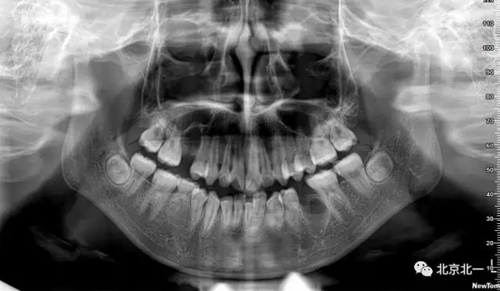

圖一:拔牙前影像片(CBCT)

術(shù)后拍片